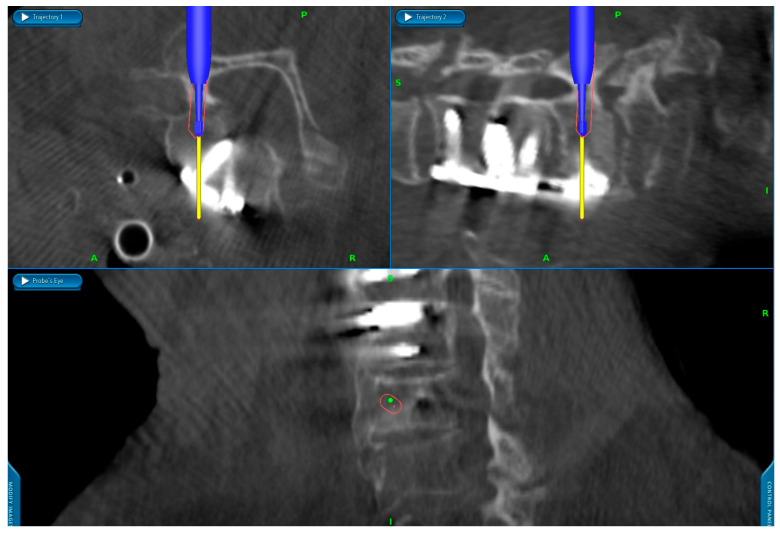

背景/目的:虽然具有生物力学优势,但颈椎椎弓根螺钉置入在技术上具有挑战性,因此通常只能在导航的帮助下在中心进行。本研究的目的是在一项大型单中心队列研究中,利用术中成像和使用导航高速钻头的工作流程分析导航颈椎椎弓根螺钉(CPS)置入的准确性和安全性。方法:我们对2018年1月至2024年6月期间接受后路颈椎或颈胸内固定术的205例患者进行了回顾性分析。使用Gertzbein-Robbins分类评估准确性,0级和1级被认为是满意的。分析手术流程、术中影像及并发症。结果:共评估椎弓根螺钉1112枚,其中颈椎螺钉888枚,上胸椎螺钉224枚。0级801例(72.0%),1级250例(22.5%),2级56例(5.0%),3级5例(0.4%)。93.1%的颈椎螺钉置入0级和1级满意,100%的上胸椎螺钉置入满意(0级92.0%,1级8.0%)。3级骨折发生在C2、C3、C5、C6和C7,各1例。无植入物相关神经血管损伤病例。结论:本研究显示螺钉精确度高,并发症发生率低。螺钉错位无翻修手术,但发生螺钉松动7例。然而,回顾性设计和对术中影像的依赖限制了结果的普遍性。

Background/Objectives: While biomechanically superior, cervical pedicle screw placement is technically challenging, and therefore typically performed only in centers with the aid of navigation. The purpose of this study was to analyze the accuracy and safety of navigated cervical pedicle screw (CPS) placement using intraoperative imaging with a workflow using a navigated high-speed drill in a large single-center cohort. Methods: We conducted a retrospective analysis of 205 patients undergoing posterior cervical or cervicothoracic instrumentation between January 2018 and June 2024. Accuracy was assessed using the Gertzbein-Robbins classification, with grades 0 and 1 considered satisfactory. Surgical workflow, intraoperative imaging, and complications were analyzed. Results: A total of 1112 pedicle screws, including 888 cervical and 224 upper thoracic screws, were evaluated. 801 were grade 0 (72.0%), 250 grade 1 (22.5%), 56 grade 2 (5.0%), and 5 grade 3 (0.4%). Cervical screws achieved satisfactory placement grades 0 and 1 in 93.1%, and upper thoracic screws in 100% (92.0% grade 0, 8.0% grade 1). Grade 3 breaches occurred in C2, C3, C5, C6, and C7, with one case each. There were no cases of implant-related neurovascular injuries. Conclusions: This study demonstrates high screw accuracy with a low observed complication rate. No revision surgeries were required due to screw malposition, but 7 cases of screw loosening occurred. However, the retrospective design and reliance on intraoperative imaging limit the generalizability of the findings.